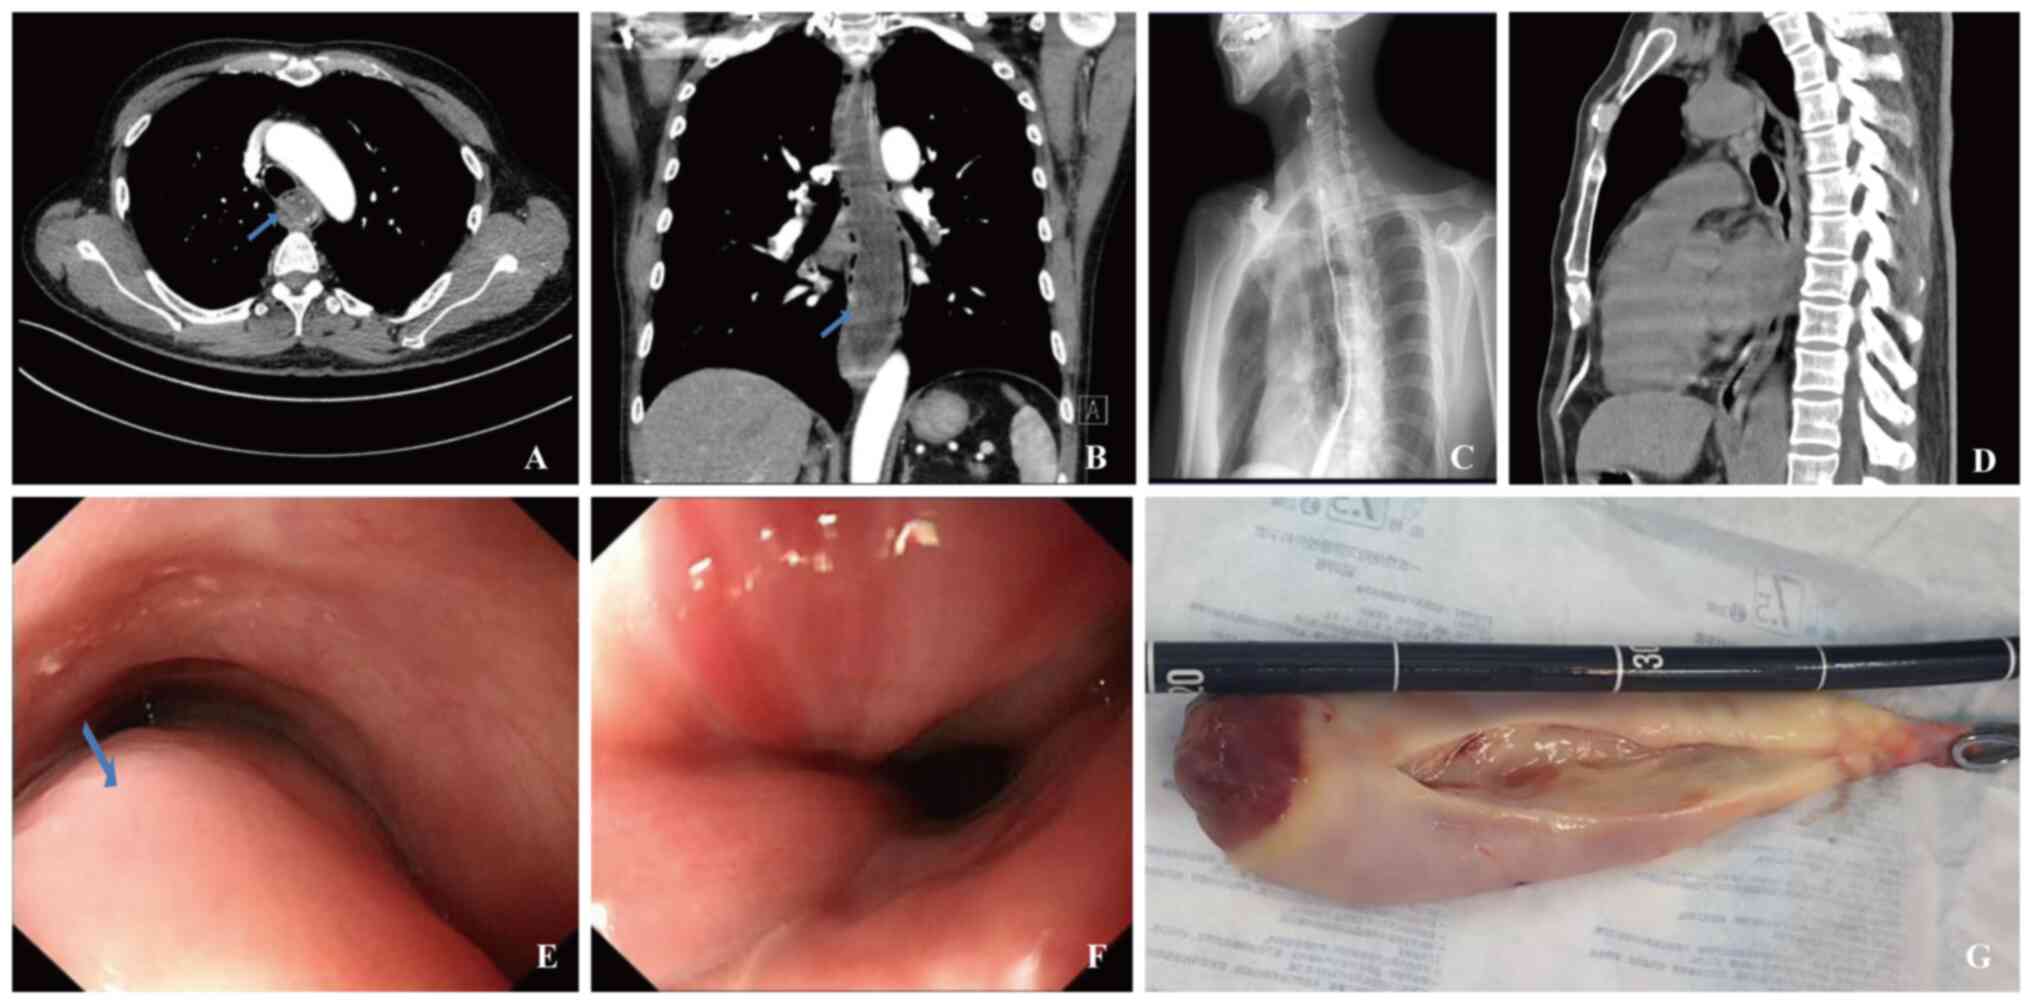

Discussion on surgical approaches for giant, well‑differentiated liposarcomas of the esophagus: Report of two cases

Giant liposarcoma of the esophagus is an exceedingly rare esophageal tumor with complex treatment options. This study investigated the treatment modalities and reported on the clinical outcomes of two cases involving giant, well‑differentiated liposarcoma of the esophagus, providing a reference for the management of similar cases. Both tumors measured >20 cm in length and had diameters exceeding 4 cm; one case exhibited a lobulated appearance with visibly expanded blood vessels on its surface. Following discussions within a multidisciplinary team, under general anesthesia with tracheal intubation, the endoscopy team conducted endoscopic submucosal dissection, collaborating with the thoracic surgery team to manage potential bleeding risks. Both patients successfully underwent endoscopic tumor removal with postoperative pathology confirming the presence of well‑differentiated liposarcoma and no observed complications. For patients with giant and complex well‑differentiated liposarcomas, endoscopic dissection in conjunction with multidisciplinary collaboration represents a safe and effective treatment option, ensuring complete tumor removal while minimizing surgical trauma and enhancing patient prognosis.